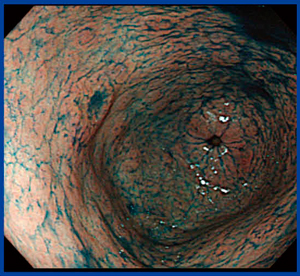

X線検診の追加撮影で,もう1回バリウム造影剤を流すことは,内視鏡検査でインジゴカルミン色素を散布することと同義である。本症例の内視鏡画像でも,インジゴカルミン色素によって前壁の棘状の変化がはっきり見えるようになった(図2)。最近では,NBI(narrow band imaging)や酢酸法なども行われている。

図2 インジゴカルミン色素を散布した内視鏡画像 |